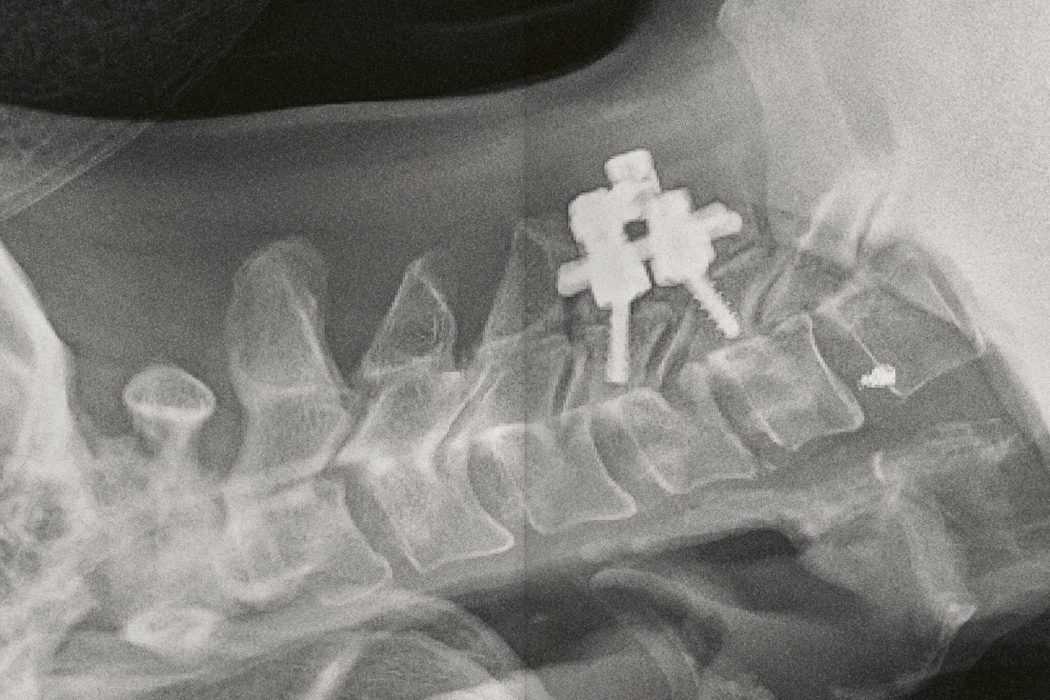

Sergio Castañeira cuenta en primera persona el momento en que cambió su vida. «El 15 de agosto de 2014 sufrí un accidente por una zambullida en la playa de Zahora (Cádiz) que me provocó una lesión medular a la altura de la cervical C5. Quedé en silla de ruedas y perdí, entre otras cosas, la capacidad manipulativa de mis manos para siempre. Soy tetrapléjico. Tras pasar un año en el hospital, ingresé en el CRMF de San Fernando, un centro de rehabilitación para lesionados físicos y psíquicos perteneciente al IMSERSO. Estuve en él desde noviembre de 2015 hasta marzo de 2020 (justo cuando comenzó la pandemia).